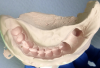

Figure 11: An initial, unrefined temporary bridge inside a preoperative impression just after removal of the preoperative impression from the mouth; material that has overflowed the

abutment margin(s) will be cut away with scissors while the temporary restoration is still soft.

Figure 11